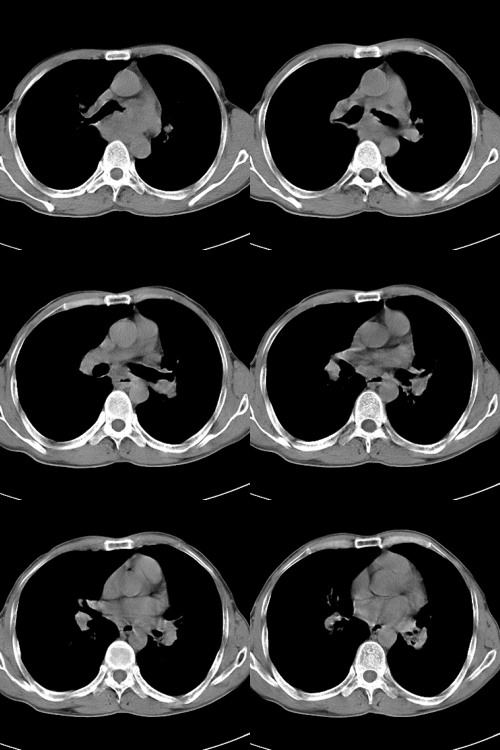

以下是引用zsl6918在2009-2-7 7:38:00的发言:[br]恶性度极高的肺癌,肺门及纵隔淋巴结转移。

以下是引用余辉在2009-2-7 8:29:00的发言:[br]考虑左下肺周围型肺癌伴肺门、纵隔淋巴转移及右肺转移